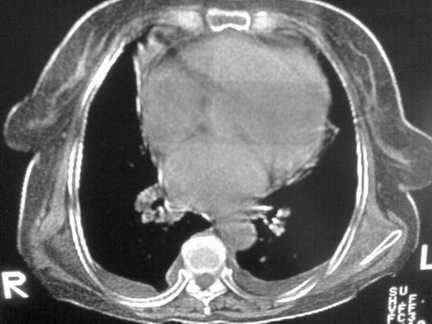

标题: CT13142:女 80 胸闷、气短、1w [打印本页]

标题: CT13142:女 80 胸闷、气短、1w

双侧胸腔积液

缩窄性心包炎

左室为主的心脏增大。

右肺感染;双侧胸腔少量积液,心影增大,可能与心功不全有关;胸内甲状腺肿。

右肺炎性变,双侧甲状腺肿,胸膜肥厚,心影增大考虑心功能不全.

胸内甲状腺肿;右肺中叶感染;双侧胸腔少量积液;心影增大,考虑有心功能不全。